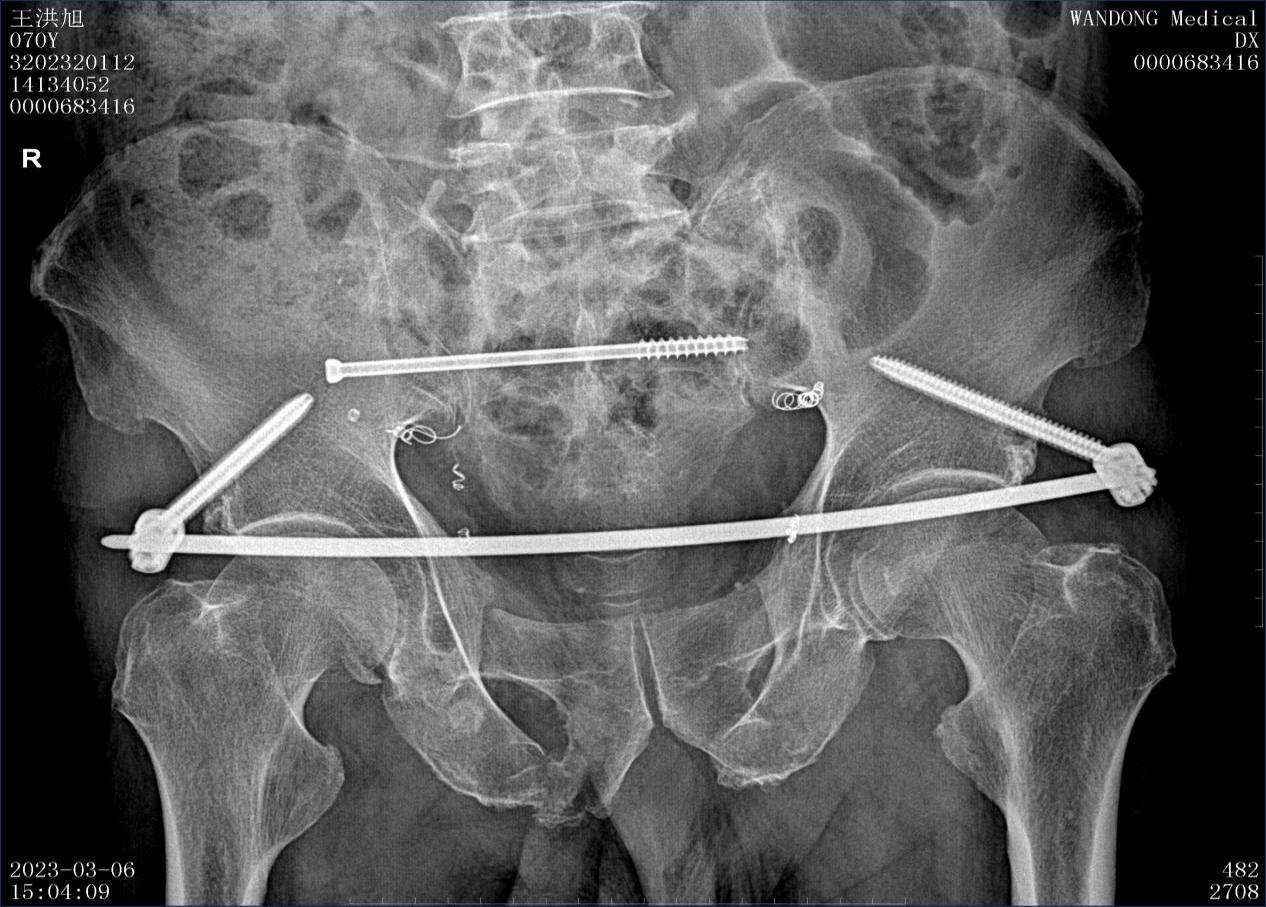

作品所属领域:骨科

安徽省 六安市 六安市第四人民医院

张杨 骨科 科主任